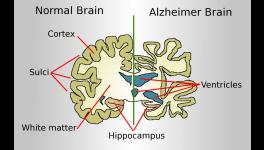

Brains without (left) and with (right) Alzheimer’s disease; Figure courtesy Science Magazine

The diversity of human brain function may not be encoded within a constant genetic blueprint; neurons can reshuffle their genes, a new study published in Nature reveals. This modification of the neurons’ genetic architecture may increase the protein variety in the brain, but it may also be related to Alzheimer’s disease, the study suggests.

The researchers analysed neurons from six healthy elderly people and seven patients reported to have Alzheimer’s disease. The patients had the most common form of Alzheimer’s - the non-inherited one. The researchers tested whether the brain cells got different forms of the gene for amyloid precursor protein (APP). Amyloid is the protein that forms plaques in the brain cells of people suffering from Alzheimer’s disease. The researchers considered APP as a good candidate because in a previous study they found that the gene for APP can have extra copies in the cells of Alzheimer’s patients. The increase arises from the process of somatic gene recombination.

What is more interesting, the Nature paper reports that the APP gene doesn’t make one or two extra copies, in fact, it produces thousands of different versions of the gene. In some of the versions, single nucleotide bases, the building blocks of the genetic code, are switched while in other versions they found that a portion of the DNA is removed and the remaining portions knitted together. They confirmed that neurons of Alzheimer’s patients contain six times more varieties of the APP protein than healthy people.